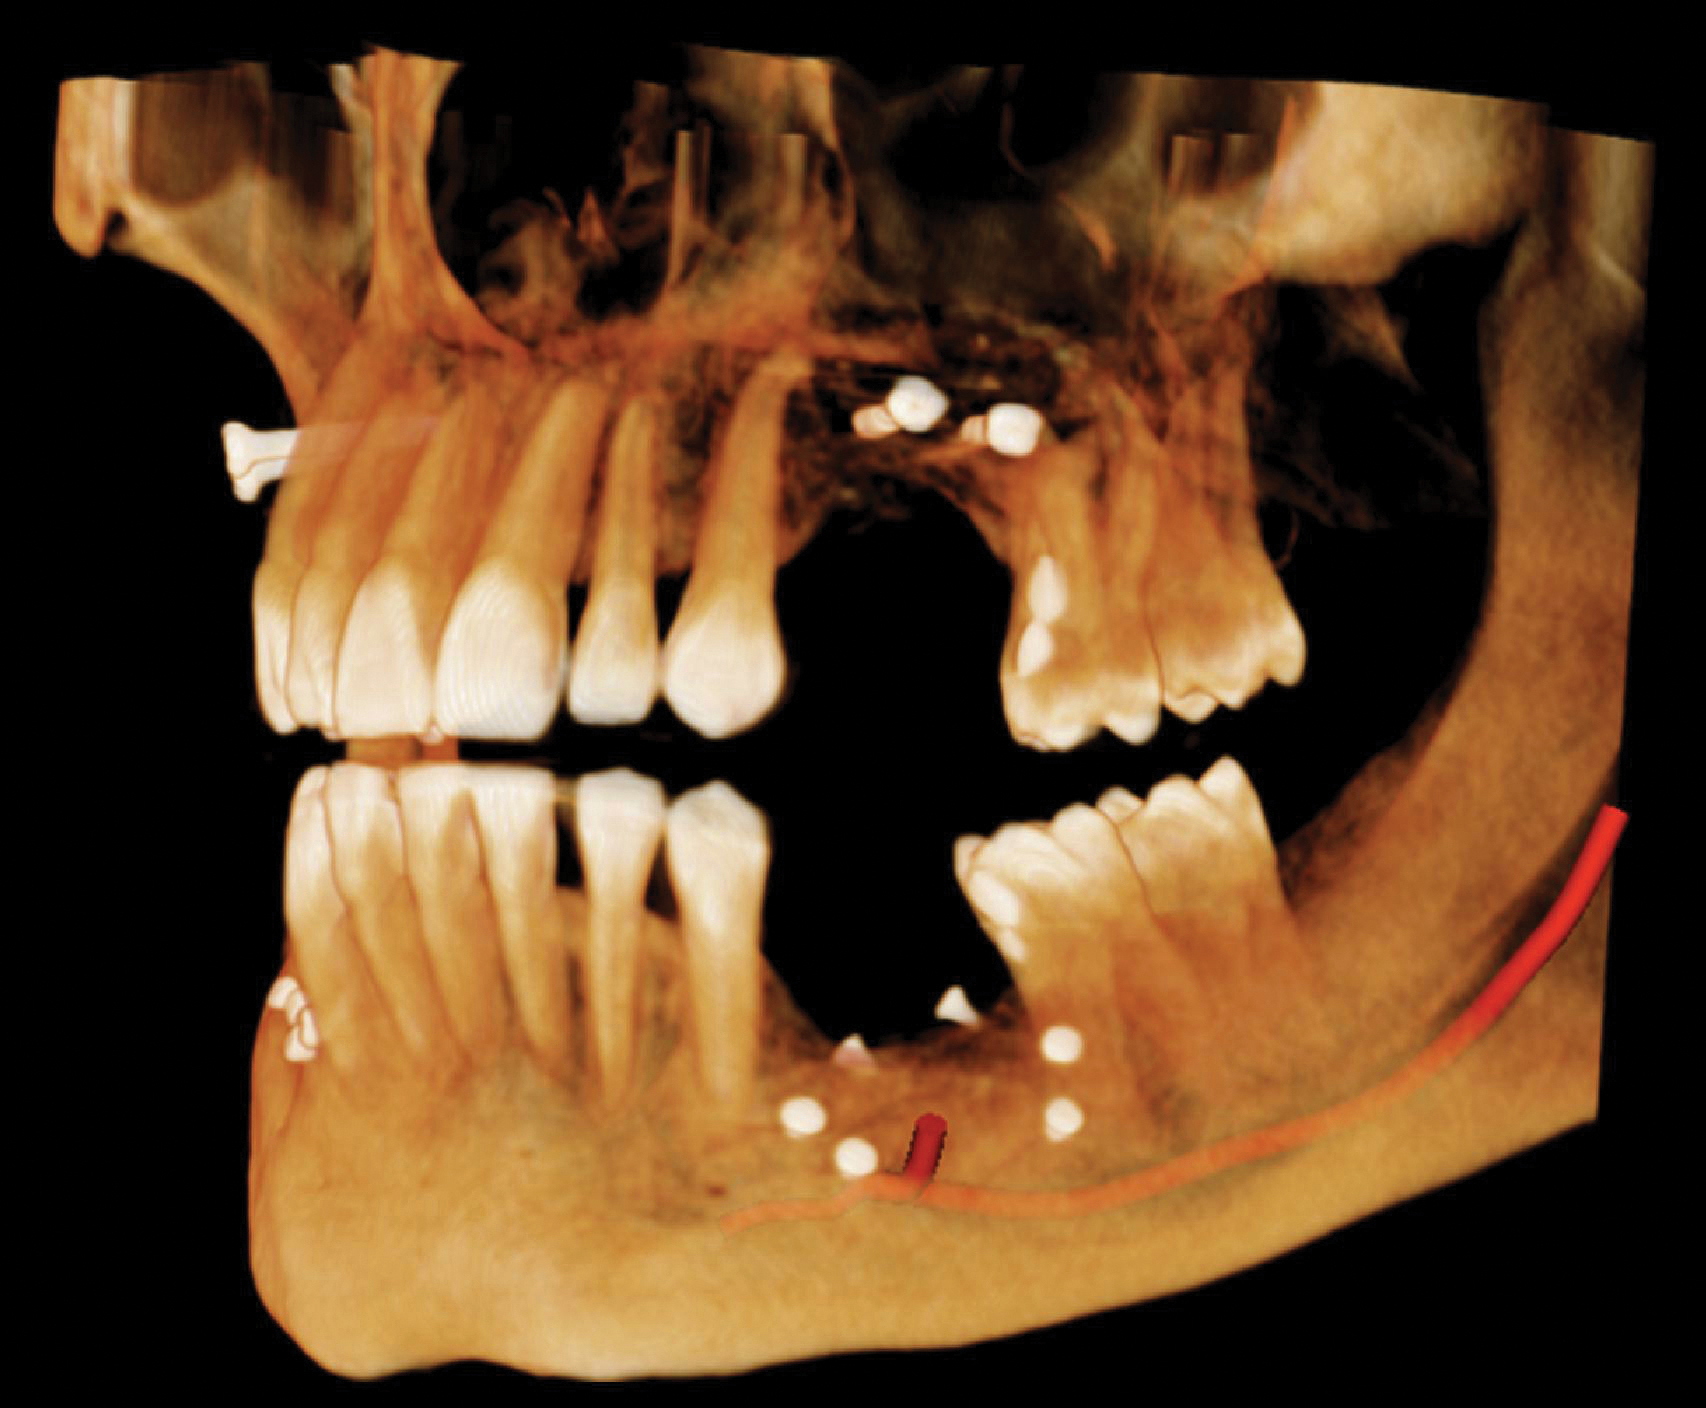

当院には正確で安全な治療を行うための検査機器をとして、最新鋭の歯科用CTシステムを導入しております。このシステムは、低い被ばく線量(総合病院などの医科用CTの1/10以下)で、3次元データの情報を得ることができ、これまでのレントゲン検査の診断が難しかった部分の診断も行えます。これにより患者さんのへのわかりやすい説明と更なる治療成績の向上が見込めます。